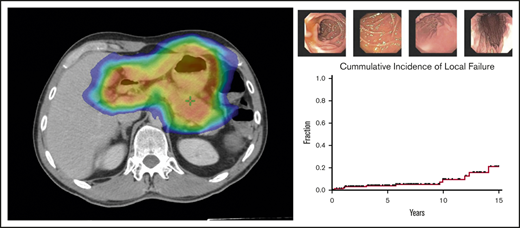

Treatment response to radiotherapy was assessed at 3 months by follow-up EGDs with multiple biopsies (Figure 2). Among the 166 patients who were treated for early-stage GML, posttreatment EGD with biopsy was performed in 160 patients, of whom 152 (95%) demonstrated a complete pathologic response (Wotherspoon 1-2) on the first posttreatment biopsy. Patients were serially followed by EGD biopsies in increasing intervals of 3 to 24 months.

EGD images documenting pathologic complete response. EGD images from patient 6, whose experienced spontaneous normalization without salvage treatment.

Over this extended follow-up period, 15 of 160 patients (9%) were found to have residual disease on EGD posttreatment biopsy (Wotherspoon 5; Figure 3). In addition, atypical lymphoid cells, not diagnostic of lymphoma (Wotherspoon 3-4), were described in 15 of 160 patients (9%). Six of the 15 patients (40%) with residual lymphoid cells subsequently progressed to local failure. Three of 20 patients (15%) with posttreatment residual disease experienced spontaneous resolution of their pathologic abnormalities on subsequent biopsy and, thus, were considered free of disease. The median interval from last radiation treatment to spontaneously resolved biopsy was 9 months (range, 8 months-3 years).

Natural history of EGD abnormalities. Fifteen patients who presented with early-stage GML exhibited residual GML on posttreatment EGD biopsy. Pathology review reported no evidence of disease (green circle), atypical lymphoid cells (blue circle), or residual GML (red open circle). Five patients with atypical lymphoid cells subsequently progressed to local failure (patients 2, 3, 4, 5, and 9). Three patients (6, 8, and 14) had pathologic EGD failures that self-resolved with observation alone.